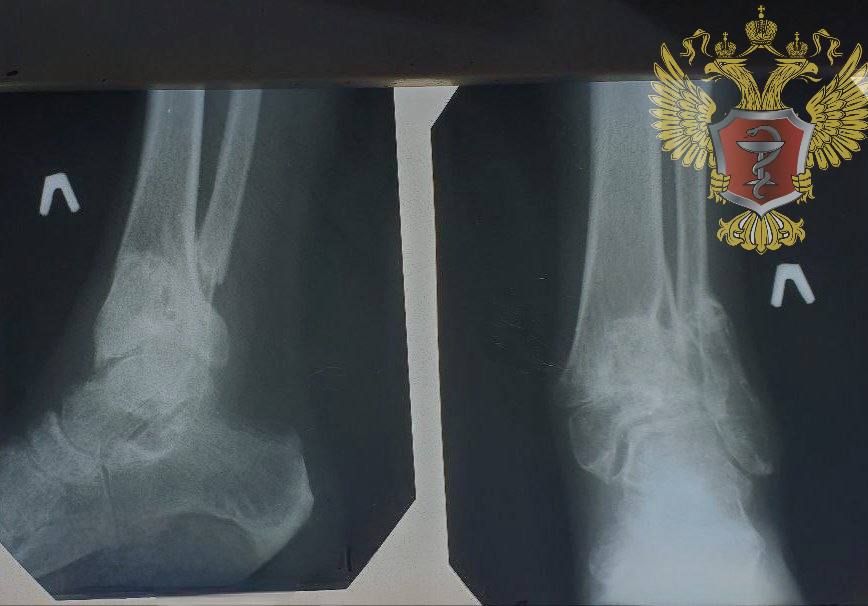

Первую высокотехнологичную операцию в Херсонщине провел травматолог-ортопед из Нижнего Новгорода в Генической больнице «У нас состоялось очередное знаковое событие уходящего года – травматолог-ортопед из Нижнего Новгорода провел первую в...